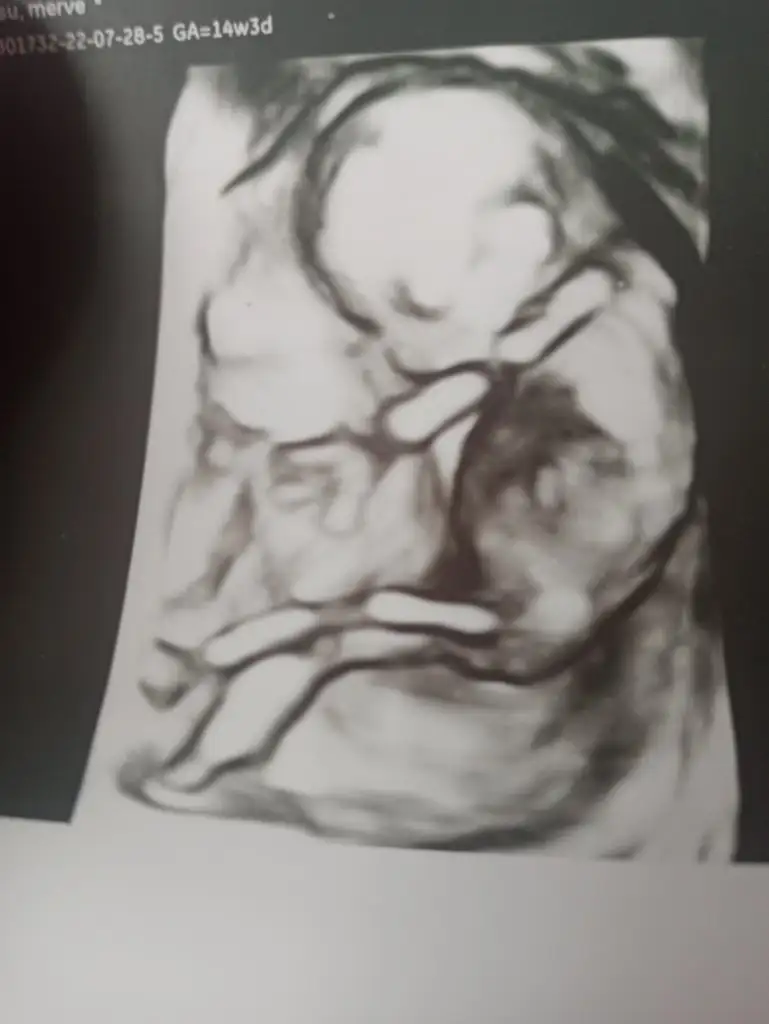

Bebeğimin cinsiyeti

Kafana takıldiysa bi doktora daha gidip sor ama bence korkacak birsey yok eli kolu oluşmuş, maşallah sıkıntısı yok belli ultrasonda bide sanki erkek gibi ne bilim kese fasulye tam😅

Yuvarlak keseye erkek diyorlardı sanki 😂 bir de ramzi miydi o teori ona göre solda ise erkek ama vajinalde tersi oluyor demişlerdi. Bakıyorum ikisinde de solda alttaki normal ultrason

Ben de fasulye diye biliyordum atmis olabilirim 😅Ramzi bende tutmadı canim, büyük olasilikla erkek dediler bize 🤔

Ben kız gibi hissediyorum ama artık hiç emin olamiyorum. 😂 Kız isimleri bakıyordum kız eşyalarına bakıyordum. Erkek derse bana şok geçiririm. Senin belli oldu o zaman. Çok erken değil mi 16. Haftada belli oluyor diye biliyordum ben.

Canim benimki de önden gidiyor , erken döllenme dediler 11. Haftada detaylı ultrasona girdim, 12 haftalık çıktı ve büyük olasilikla erkek dedi detaylıda doktor, ben de kiz diyordum ama yanıldım😅 gene yüzde yüz belli değil ama detaylı fotoda cikintisi bile gözüküyor benimkinin😅